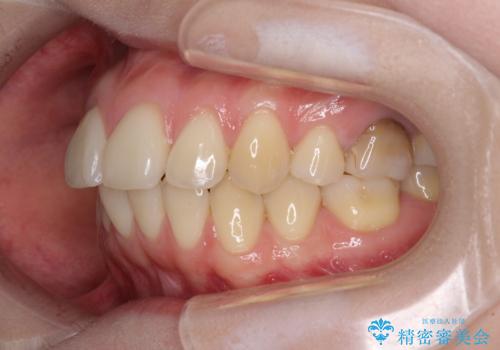

後戻りをインビザラインでスッキリした口元に

- 高校生の時に矯正治療を行ったものの、後取りをしてしまったとのことで来院された患者様です。

マウスピースでもワイヤー矯正でも対応可能でしたが、再度ワイヤーは装着したくないとのことでインビザラインにて矯正治療を行うこととしました。

舌の突出癖が原因で後戻りをしたため、舌のトレーニングをしっかりと行っていただき、口元の突出感を改善することができました。

インビザラインの装着時間が守れず、1年強で終わる予定でしたが、4年間を要することとなりました。